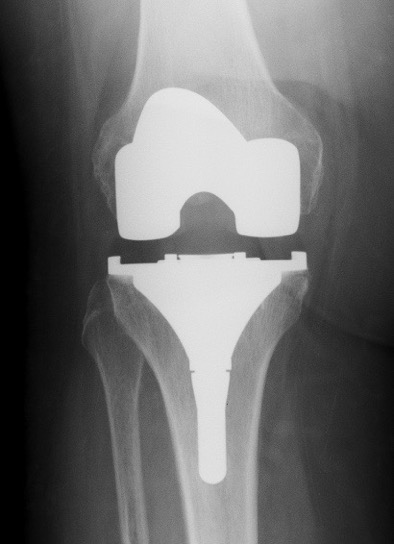

C. PTG de révision

Si faiblesse des ligaments latéraux

Si grandes déformations ou changements de prothèse

quilles d’extension dans le fémur et le tibia pour mieux répartir ces contraintes